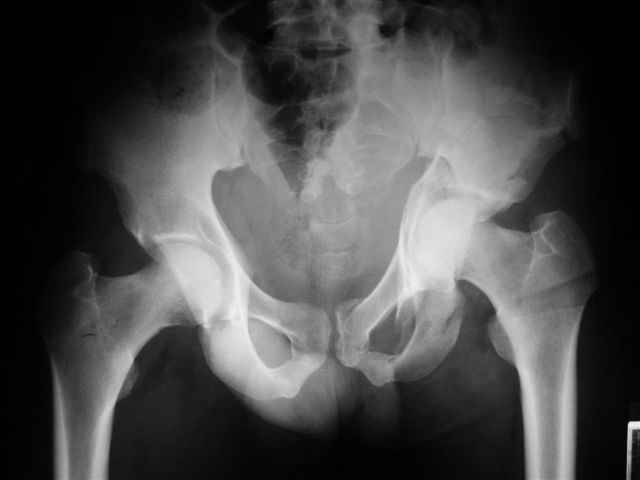

Уважаемые коллеги,43 летний мужчина, попав в автоаварию 13.10.2004, получил оскольчатый перелом обеих колонн левой вертлужной впадины.

На рентгенограммах - высокий двухколонный перелом вертлужной впадины с нарушением конгруэнтности, имеется обратная клиновидность суставной щели.

Спасибо за комментарии и рекомендации. Откровенно говоря, больного я прооперировал на прошлой неделе, через 5 дней после аварии и проблем с ним пока никаких нет, на удивление при достаточно обширной диссекции (илиофеморальный доступ) болей практически нет, так что больной самостоятельно садится в кровати, выполняет активные движения в оперированном суставе, сгибая до 60 градусов пока, далее с ассистенцией.

Причиной обращения к сообществу были возникшие непосредственно после операции сомнения и разочарования полученным качеством репозиции: а надо ли было трогать перелом вообще, репозиция передней колонны технически была очень сложна для меня, хотя реконструкции была в той же последовательности, что Д-р А.В.Рунков рекомендовал, в какой-то момент безуспешных манипуляций стал думать о *вторичной конгруэнтности*, которую не так давно обсуждали на

форуме и скелетном вытяжении. С репозицией и фиксацией задней колонны и отдельно задне-верхней стенки впадины проблем не возникло. Послеоп. Рг граммы в приложении. Если возникнут какие-либо дополнения или поправки - был бы признателен.